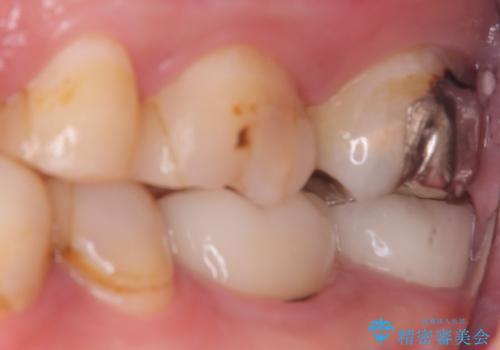

【セラミッククラウン】インレーの下の大きな虫歯

- レントゲンにて昔入れたインレーの下に虫歯が見つかった患者様です。

歯髄に近接する虫歯でしたが、根管治療は必要なくクラウンにて修復を行うことができました。